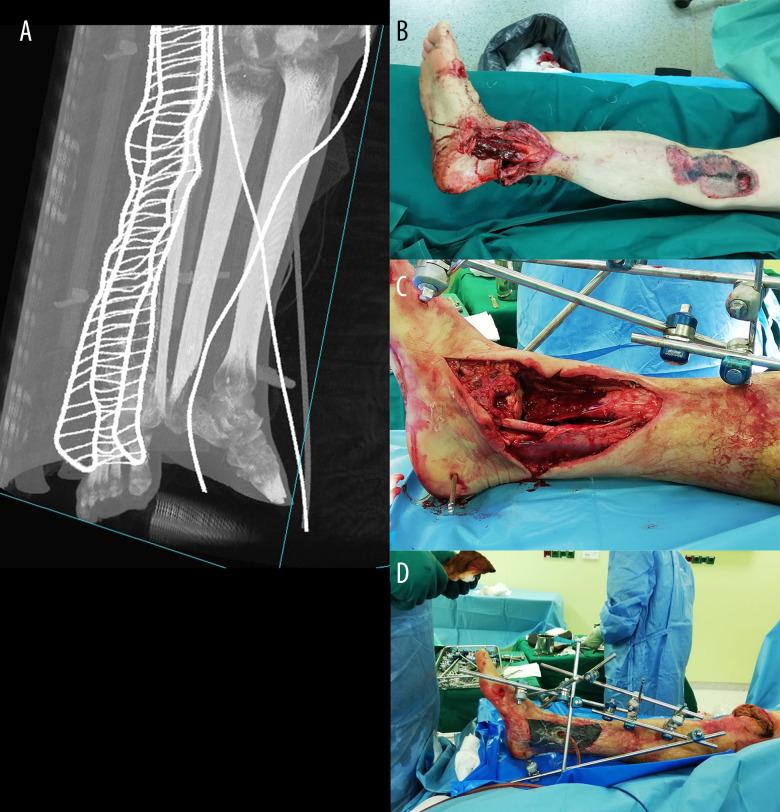

BACKGROUND In this case report, an alternative way of treating Gustillo-Anderson IIIB type fractures with severe soft-tissue damage is provided for cases where, for various reasons, it is not possible to close a soft-tissue defect with a flap. CASE REPORT An artificial deformity-creating technique was applied for a patient with a right distal tibial open fracture (Gustillo IIIB type) with complete tibial cartilage and bone loss of 10 cm and severe soft-tissue defect after high-energy trauma. This technique includes damaged limb shortening, translation, angulation, and rotation for closure of soft-tissue defects using orthopedic hexapod and bifocal bone transport without need for plastic surgery. Because of the timely planning and application of the orthopedic hexapod for the artificial deformity correction, the final alignment of the limb was close to the physiological standard and had good functional outcomes. Despite the extremely severe shortening and acute angles, the total treatment time was only 75 weeks. At the 1-year follow-up after treatment completion, the patient had good functional outcomes with the 36-Item Short Form Survey score: general health, 80%; physical functioning, 85%; and social functioning, 100%. CONCLUSIONS In conclusion, we show that the artificial deformity-creating with subsequent orthopedic hexapod application and lengthening of a limb is a robust method that can be applied even for the treatment of severe open fractures with significant soft-tissue damage and bone loss, which can be performed outside high-level trauma hospitals and has good clinical outcomes without significant complications.